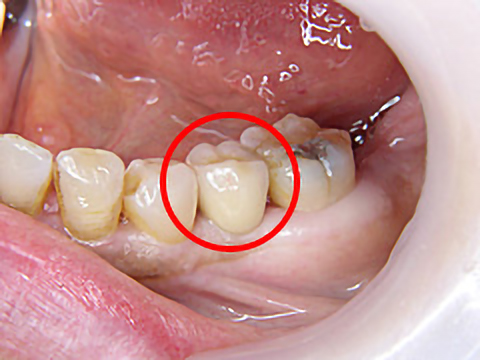

歯科治療が怖くて長きにわたりお口を放置されていましたが、一大決心の後、当院にて治療を受けられました。

右上4本、左上も3本、抜歯即時埋入を含めてインプラント治療を受け、噛み合わせを取り戻すことができました。また、下顎の前歯も大きくすり減っていたため、オールセラミックスで治療しました。